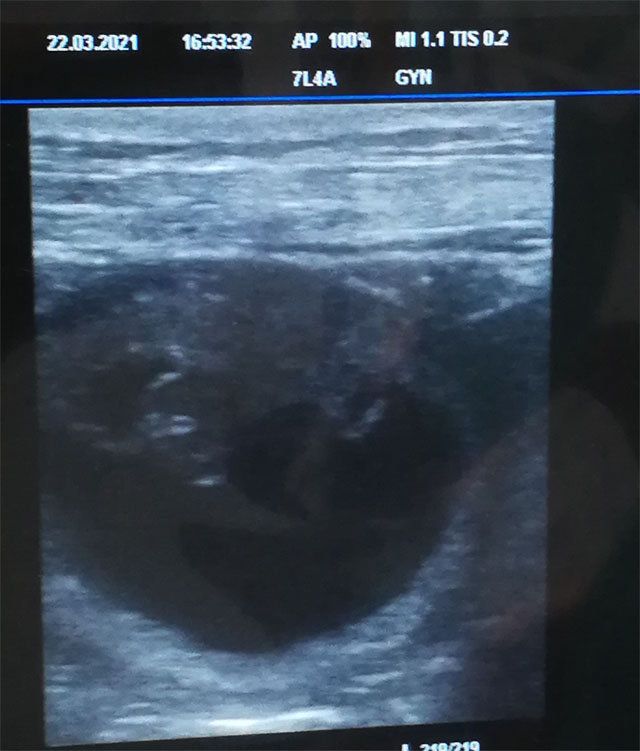

22.03.2021 (32. Tag)

Heute war der ersehnte Ultraschalltag. Nachmittag hatten wir einen Termin.

Es ist immer sehr spannend ob es geklappt hat und die Hündin tragend ist. Ich habe Merida auf dem Untersuchungstisch hochgehoben und dann wurde der Ultraschallkopf an den Bauch gesetzt und schon haben wir einige Fruchtanlagen gesehen. Wieder Zuhause angekommen hat sich Merida erst einmal schlafen gelegt.

Merida und Tauno werden Eltern.

| Ja, Merida erwartet nun Welpen. Wie geht es weiter in ihrem Bäuchlein ? |